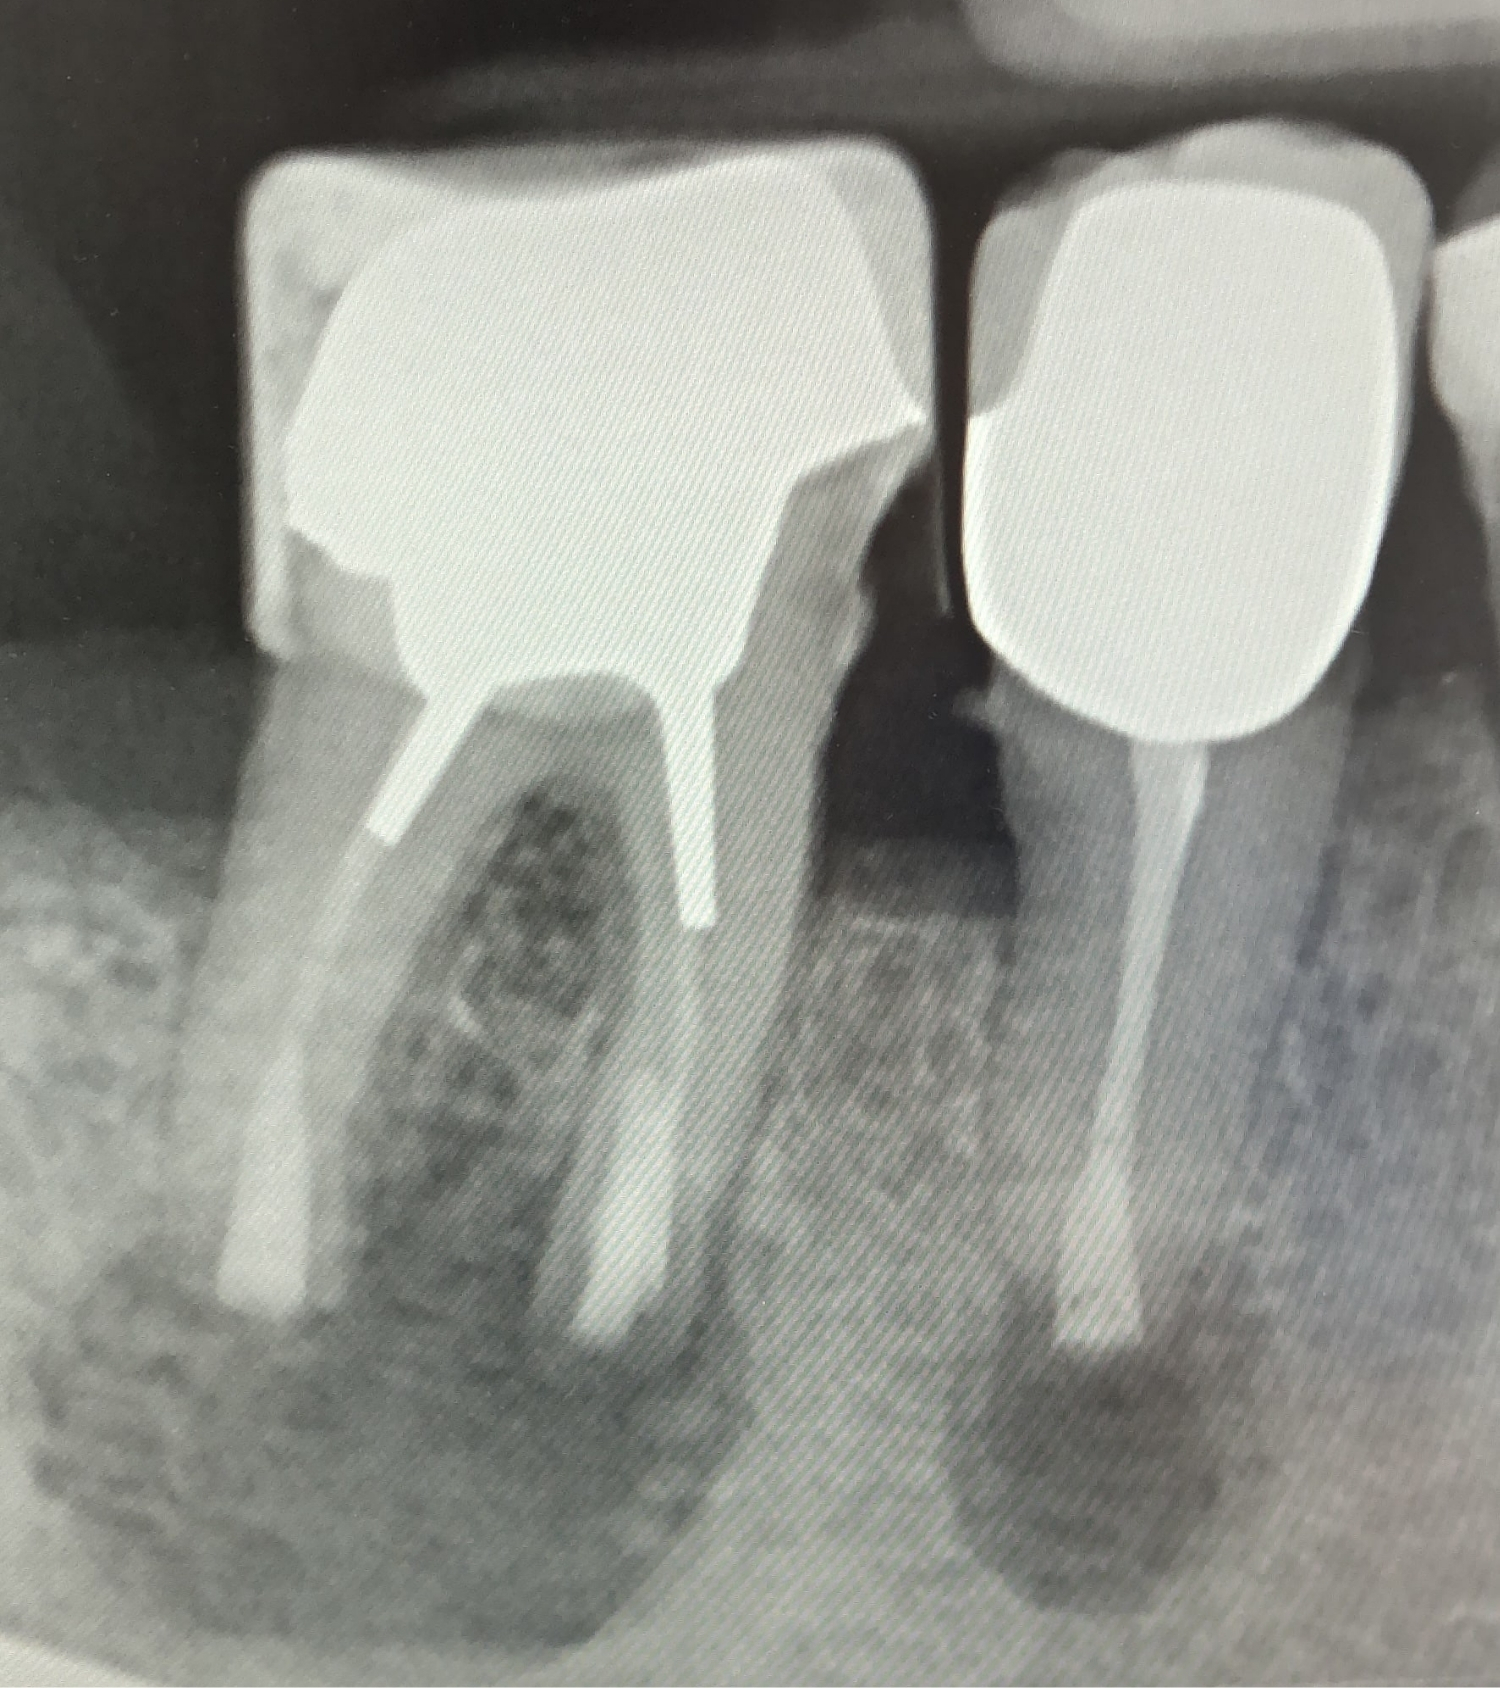

Röntgenaufnahme zweier behandelter Zähne mit Wurzelkanalfüllungen und Kronen. Die Aufnahmen zeigen die Zahnwurzeln, Wurzelfüllmaterialien und die umgebende Knochensubstanz.

Nachher